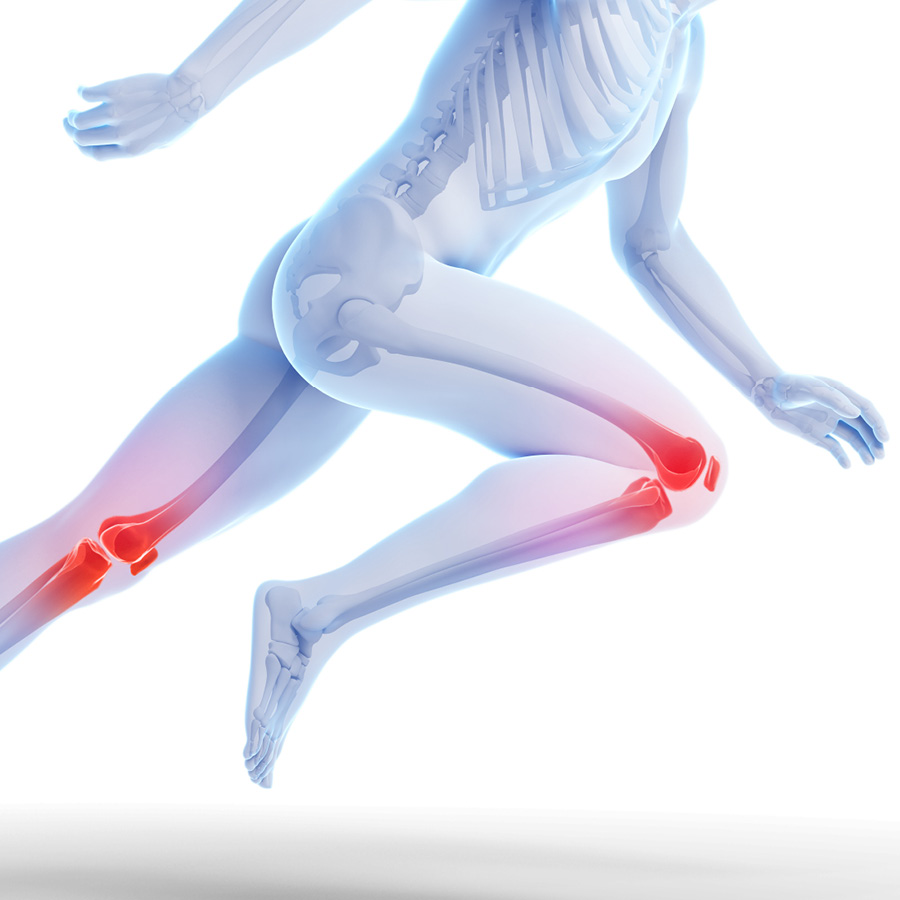

Running Injuries – Valutazione, Prevenzione, Riatletizzazione e ritorno allo sport.

Se da un lato sono ben conosciuti i benefici di una regolare attività fisica praticata nell’arco di tutta la vita, sono altrettanto ben studiati i rischi di patologie, sia traumatiche sia da sovraccarico funzionale (overuse) soprattutto negli sport di “endurance”.

“focus on knee injuries”

Come e quando un ginocchio diventa doloroso: da dove proviene il dolore ?

“Knee abusers & overlap syndrome”:

le sindromi da sovraccarico del ginocchio negli sport di durata